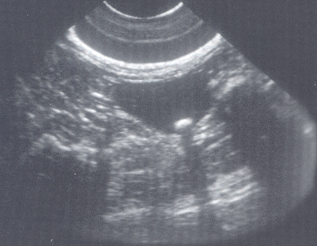

What is being shown in this bladder?

Cystolith (bladder stone) —> casting acoustic shadow